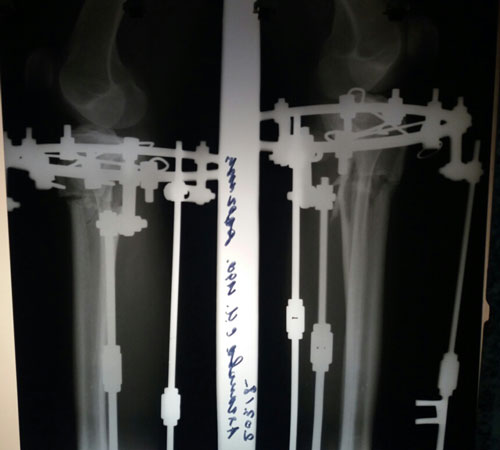

Дата операции 06.02.2018г.

Дата снтия аппаратов 02.05.2018г.

Срок лечения 86 дней.

Как мастерски исправлена такая страшная Ротация!